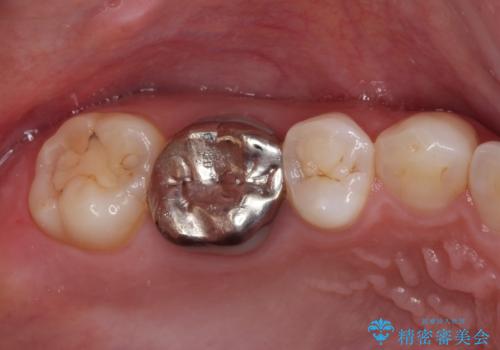

- 奥歯の銀歯が外れたことをきっかけに、全ての銀歯をセラミックに替えたいとのことで来院された患者様です。

第一大臼歯4本と、メタルインレーが装着されている2歯をセラミッククラウンならびにセラミックインレーにて補綴治療・修復治療を行うこととしました。